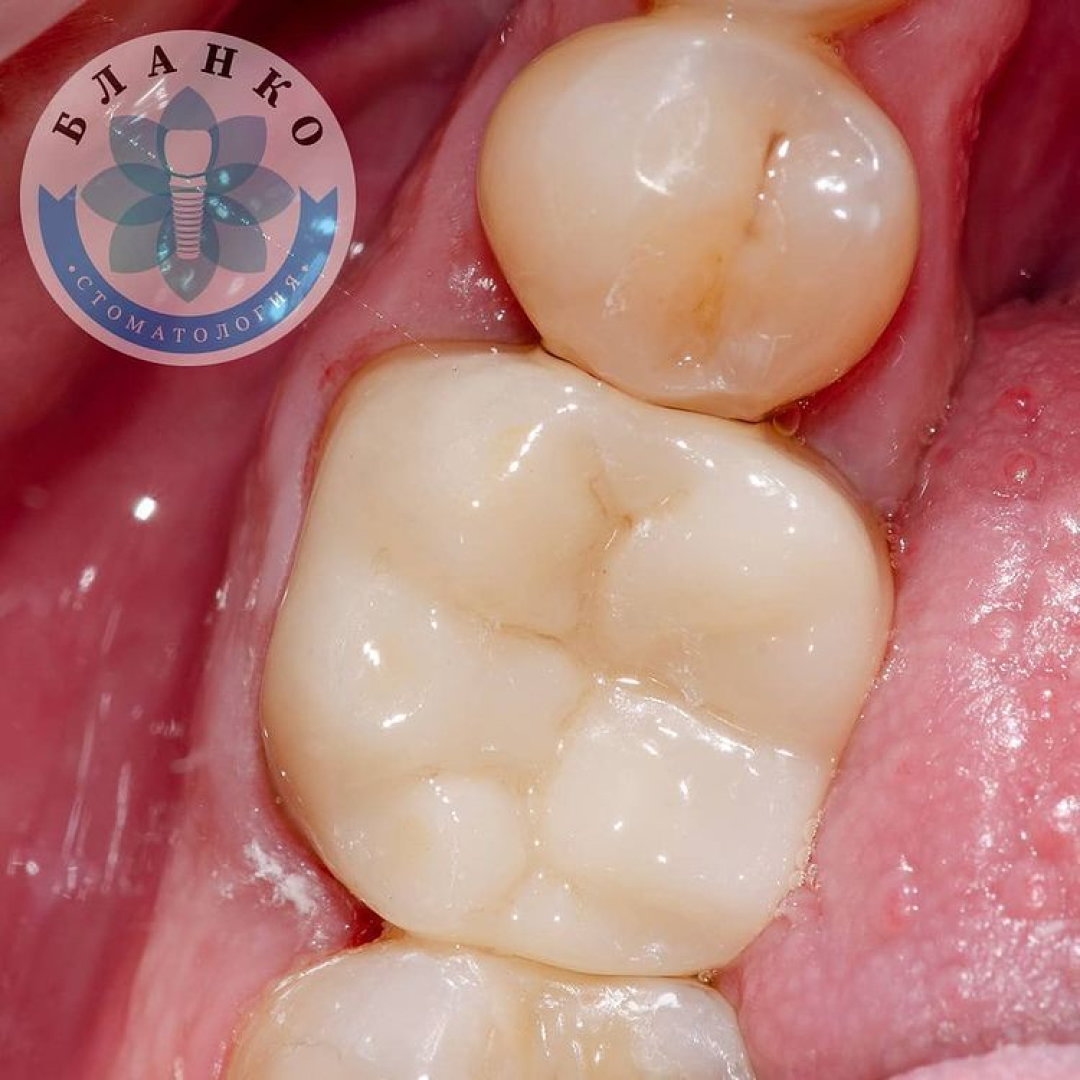

— твердые ткани зуба восстановлены с помощью специального материала

— сняты оттиски и изготовлена высокопрочная, гипоаллергенная и высокоэстетичная коронка из диоксида циркония.